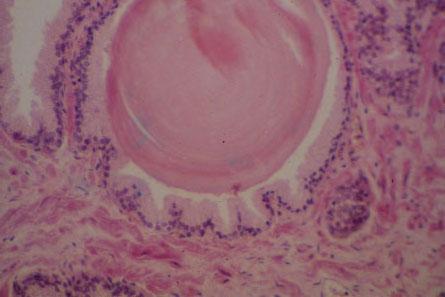

XI-20 (4) Demo slide, Prostate Gland (H&E), high power. Branched tubuloacinar glands are contained within a fibromuscular stroma. A prostatic concretion (corpus amylacea) is seen.